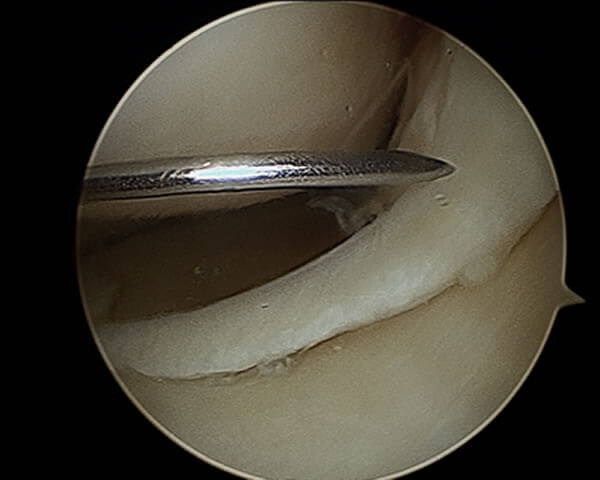

L'arthroscope (photo) est un tube de quelques mm de diamètre, couplé à une caméra vidéo miniaturisée, elle-même reliée par un cable optique à un écran de télévision couleur. L'image est très agrandie : le crochet que vous pouvez voir sur la photo mesure 3 mm dans sa partie verticale...

L'arthroscope est introduit à l'intérieur du genou par un orifice minime ; un ou parfois plusieurs autres petits orifices cutanés sont nécessaires pour l'introduction d'instruments fins dans l'articulation. Pendant tout l'examen, le genou est gonflé avec du sérum physiologique.